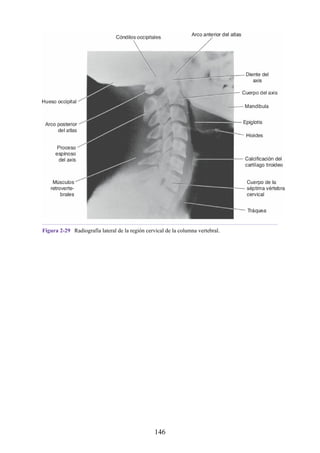

gestante o por un tumor ovárico grande; también puede ser consecuencia de una patología de la

columna vertebral, como espondilolistesis. La lordosis lumbar también puede presentarse como